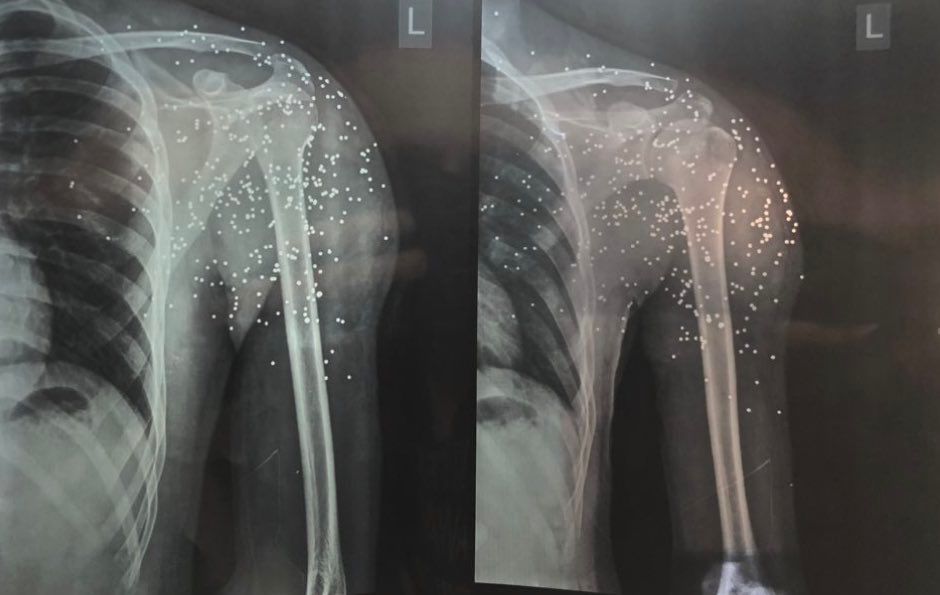

He said if he fails to refer them to his trusted doctors in Iran, he tries to walk them through the best home remedies possible. According to him, their injuries range from fractures and significant head injuries, to second- and third-degree burns from electric batons, as well as bullet and pellet wounds.